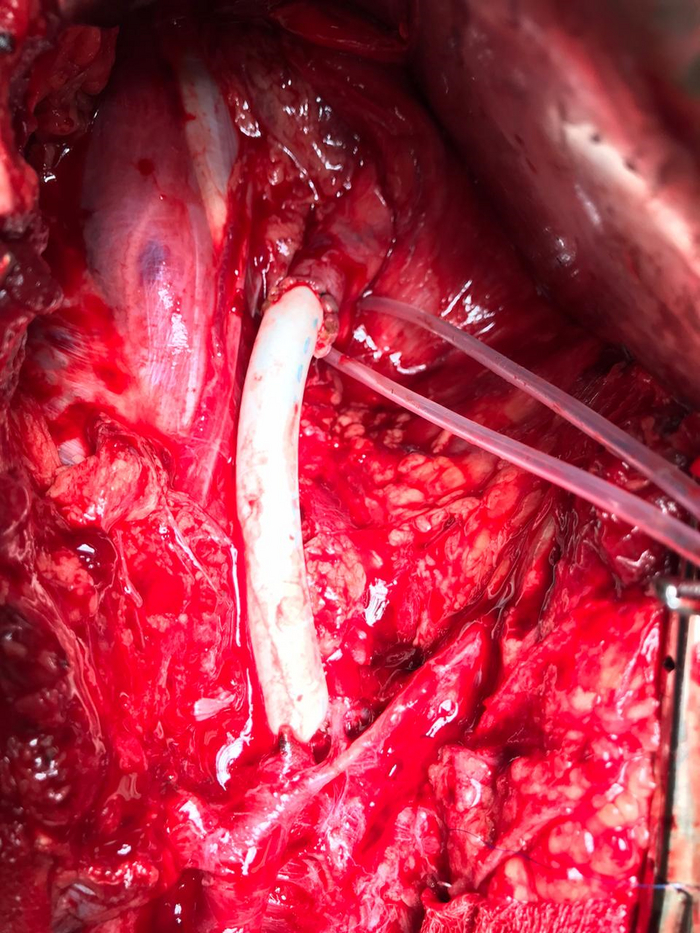

Соответственно, открыто можно пришить шунт

Беленькая штучка - это искусственный сосуд. Но можно использовать и собственную вену, если она по размеру подходит))